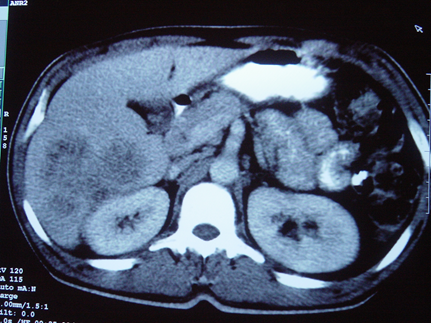

NEYROENDOKRİN TÖRƏMƏLƏRİN QARACİYƏRƏ METASTAZLARI

N.Y.Bayramov, R.A.Məmmədov

Tərifi

Orqan və toxumalarındakı yerli endokrin hüceyrələrindən (karsinoidlər) və mədəaltı vəzidəki (MAV) adacıq hüceyrələrindən inkişaf edən şişlərin qaraciyər metastazlarıdır.

Gedişi

• NET metastazları yavaş böyüyən, kimyaterapiyaya az həssas törəmələrdirlər, adətən hipervaskulyar olurlar və sürətli qan axınına sahibdirlər.

• NET-in təbii gedişinə təsir edən ən önəmli amillər qaraciyərə metastaz, metastazların sayı və müalicədir: 5 illik yaşam metastaz olmayan hallarda 90-100%, metastaz olduqda 30-40%,  rezeksiyadan sonra 70%-ə çata bilir.

Dəqiqləşdirmə

• Dəqiqləşdirmək üçün klinik əlamətlərlə yanaşı endokrin müayinə, tomoqrafiya və ssintoqrafiya aparılır.

• NET-in qaraciyər metastazlarının xarakterik xüsusiyyəti hipervaskulyar olmasıdır ki, bu da Doppler müayinəsində intensiv axın şəklində, kontrastlı müayinələrdə isə arterial fazada kontrastlaşma və venoz fazada yuyulma əlaməti ilə təyin edilir.

• Hormonal aktiv şişlərdə endokrin əlamətlərlə yanaşı qanda hormonların səviyyəsi artır.

• Funksional karsinoidlərdə sidikdə 5-hidroxiindol turşusunun təyini, adacıq şişlərində isə hormonların təyini diaqnozda faydalıdır.

• Adacıq şişlərinin yayılmasını və diaqnozunu dəqiqləşdirmək üçün PET-KT və somatostatins sintoqrafiyası faydalıdır.

• Histokimyəvi müayinədə xromoqrafin A və neyron – spesifik enolazanın tapılması diaqnozu dəqiqləşdirir.

Diaqnostik əlamətləri:

• Kütlə effekti və ya endokrin əlamətlər

• 5-hidroksiindol turşusu və ya hormonların artması

• Hipervaskulyar törəmələr

• PET-KT və ya somatostatin ssintoqrafiyası müsbət

• Biopsiyada xromoqrafin A, neyronal enolaza enzimi müsbət